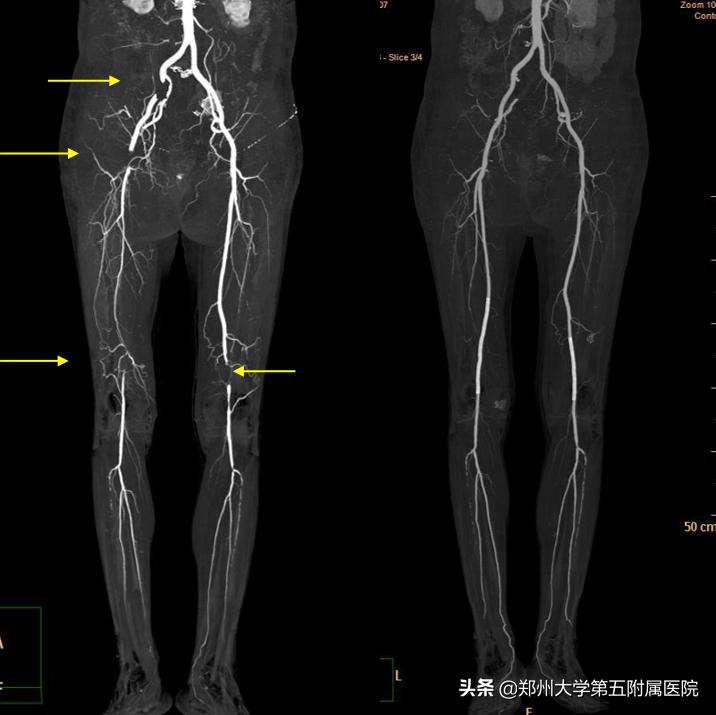

▲ 双下肢动脉多发闭塞病人,经取栓及支架植入术后,血管通畅良好